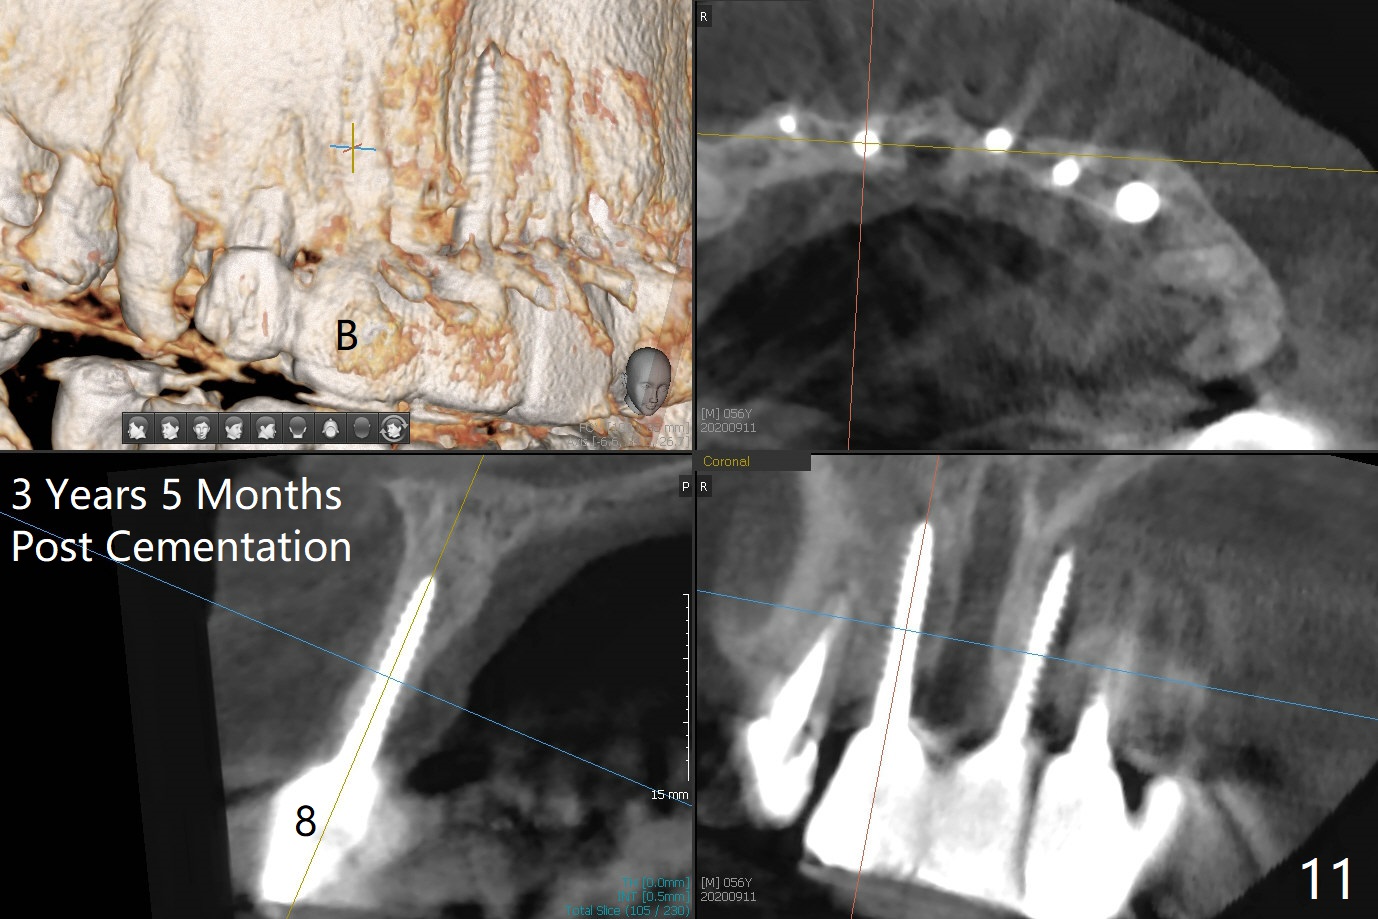

There is no obvious black triangle between the implants at #8-11 (Fig.1 post infiltration). Following papilla (Fig.2 *) sparing incision and elevation of the buccal flap, the fenetration of the buccal plate around the socket shield (Fig.3 S) is found at #11; there is a distal defect with granulation tissue (*). After shield and granulation tissue removal, the coronal implant is found exposed (Fig.4 until osteotomy). The relatively flat surface of IBS implant is apparently less likely to develop periimplantitis. With periosteal relief and placement of sticky bone (Fig.7 *), PRF and 6-month membrane, the wound is closed with 4-0 PTFE suture (Fig.5). Failure of socket shield is related to retention of the apex (Fig.6 <). Probe before extraction and remove apex and gutta percha. There appears no buccal or palatal (P) defect 9 months post shield removal (17 months post cementation, Fig.8), although the bone density palatally is low. Although the sagittal section (Fig.9 (lower left panel) shows the absent palatal plate at #10, the 3-D image and the coronal section do not (upper let and right panels). The 2.5 mm implant at #9 appears to have been placed buccal (Fig.10 B), although the buccal crest is present. In contrast the 2.5 mm implant at #8 appears within the bone boundary (Fig.11). The soft tissue remains healthy at #8-11. Bone graft will be done if needed.